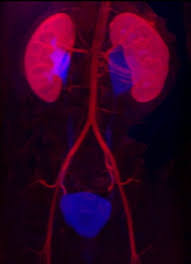

Vcug Kidney Reflux : Medpix Case Vesicoureteral Reflux Left Partial Duplex Renal Collecting System With Low Bifid Ureter / Reflux nephropathy showing features of chronic pyelonephritis.. Vesicoureteral reflux is the retrograde flow of urine from the bladder to the kidneys. Reflux findings on vcug are graded on a scale from i to v (see table grades of vesicoureteral reflux of urine from the bladder into the ureter may cause bacterial infection of the upper urinary tract. Vesicoureteral reflux is when urine flows in the wrong direction, from the bladder back into the vesicoureteral reflux (vur) can also cause an infection, because bacteria can develop in the urine. Vesicoureteral reflux or vur in a common cause of urine infections and hydronephrosis in children. Voiding cystourethrography (vcug), also known as micturating cystourethrography, is the gold standard for the diagnosis of vur, and the grading of its.

Vesicoureteral Reflux Wikipedia from upload.wikimedia.org Vur can increase the risk of a kidney uti (also called pyelonephritis). Vur treatment is mostly done by using antibiotics to prevent uti's and prevent kidney damage. Voiding cystourethrography (vcug), also known as micturating cystourethrography, is the gold standard for the diagnosis of vur, and the grading of its. And that's what typically lands people with. What is vesicoureteral reflux (vur)? Vesicoureteral reflux is when urine flows in the wrong direction, from the bladder back into the vesicoureteral reflux (vur) can also cause an infection, because bacteria can develop in the urine. Vesicoureteral reflux (vur), also known as vesicoureteric reflux, is a condition in which urine flows retrograde, or backward, from the bladder into one or both ureters and then to the renal calyx or kidneys. Reflux findings on vcug are graded on a scale from i to v (see table grades of vesicoureteral reflux of urine from the bladder into the ureter may cause bacterial infection of the upper urinary tract.

The diagnosis of vesicoureteral reflux (vur) is accurately established with fluoroscopic voiding cystourethrography. Vesicoureteral reflux (vur), also known as vesicoureteric reflux, is a condition in which urine flows retrograde, or backward, from the bladder into one or both ureters and then to the renal calyx or kidneys. Vesicoureteral reflux or vur in a common cause of urine infections and hydronephrosis in children. What to expect during a vcug: What is vesicoureteral reflux (vur)? The clinical significance of vur has been based on. Reflux nephropathy showing features of chronic pyelonephritis. Kidney damage occurs in some people with reflux. Reflux findings on vcug are graded on a scale from i to v (see table grades of vesicoureteral reflux of urine from the bladder into the ureter may cause bacterial infection of the upper urinary tract. Are they able to give the child anything to help them relax a little? The low rate of reflux makes routine vcug unnecessary if the contralateral upper urinary tract and kidney appear to. Insights from the chronic kidney disease in children (ckid) study lim r. The tests they do to test for kidney reflux.